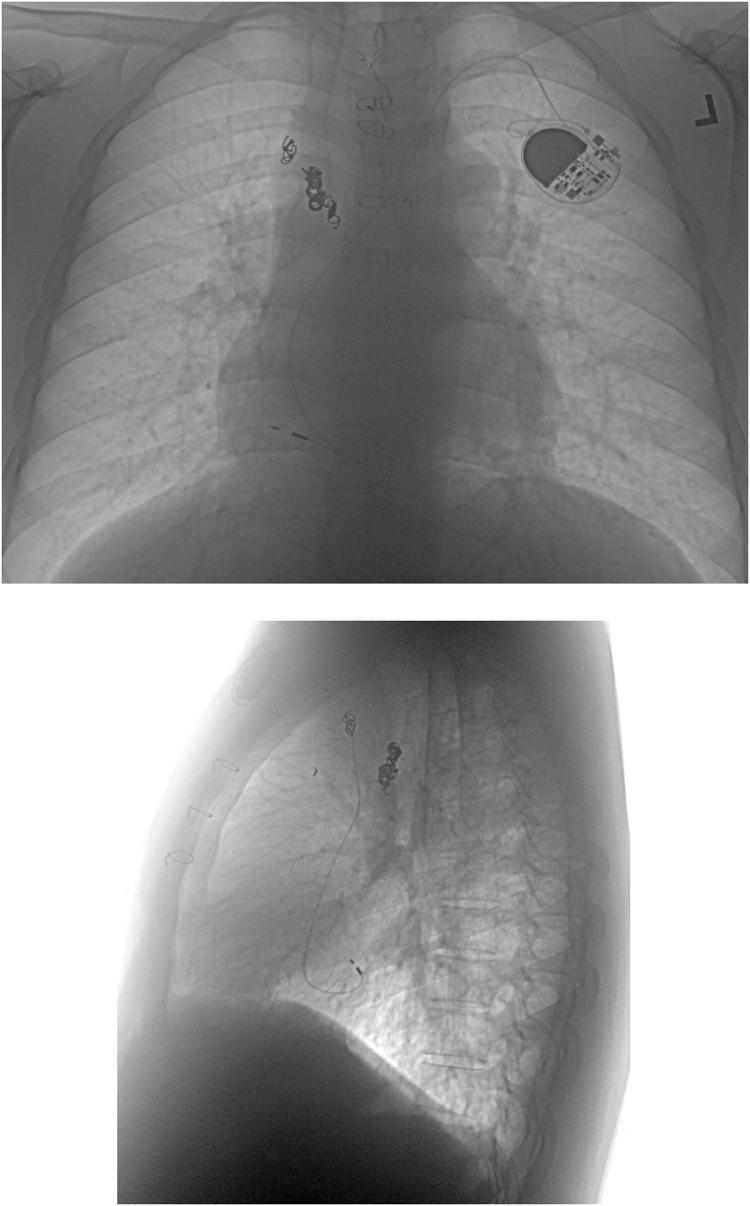

Transvenous approach to pacemaker lead implantation for sinus node dysfunction after extracardiac lateral tunnel Fontan conduit placement.

HeartRhythm Case Rep. 2016 Sep 14;2(6):495-498. doi: 10.1016/j.hrcr.2016.07.006. eCollection 2016 Nov.

DOI:10.1016/j.hrcr.2016.07.006

PMID:28491745

原文链接:https://pmc.ncbi.nlm.nih.gov/articles/PMC5419993/